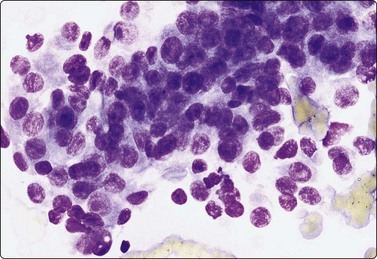

Nasopharyngeal carcinoma (NPC) (Figs 4.8, 4.9, and 5.59)44-47

image image

Fig. 4.9 Nasopharyngeal carcinoma (undifferentiated, lymphoepithelial type, WHO type III)

Loose clusters of undifferentiated epithelial cells with vesicular nuclei, prominent nucleoli and pale fragile cytoplasm. Background of lymphocytes. (A, MGG, HP; B, H&E, HP).

Criteria for diagnosis (undifferentiated carcinoma nasopharyngeal type (UCNT)/WHO type III/lymphoepithelial carcinoma)

Undifferentiated malignant cells, single and in clusters,

Variable amount of pale, fragile cytoplasm,

Large vesicular nuclei with prominent central nucleoli,

Admixture with, and background of, lymphoid cells, often with prominent plasma cells,

Ancillary tests: neoplastic cells positive for cytokeratin, negative for lymphocyte markers. EBV-associated nuclear antigen.

Nasopharyngeal carcinoma (NPC) is a clinicopathologic entity different from other squamous cell carcinomata of the head and neck. It is distinguished by its particular histology, geographic distribution, relationship to Epstein-Barr virus, and the absence of an alcohol or tobacco etiological relationship. A proportion of NPCs show squamous differentiation and the cytological pattern of non-keratinizing squamous cell carcinoma (squamous cell carcinoma/WHO type II) (Fig. 4.8). Keratinized cells (WHO type I) are uncommonly found. The majority of NPC are poorly differentiated or undifferentiated. Cells from undifferentiated NPC (UCNT, WHO type III) form loose clusters with no specific microarchitectural pattern, and are usually mixed with lymphoid cells. In the ‘lymphoepitheliomatous’ type (Schmincke-Regaud) the cells tend to be less cohesive, resembling Hodgkin’s disease or large cell non-Hodgkin lymphoma. However, in NPC, the malignant cells are still clustered and have more abundant pale cytoplasm contrasting with the lymphoid cells in the background (Fig. 4.9). Plasma cells are frequently found among the lymphoid cells. Immunostaining for cytokeratin and a pan-lymphocyte marker is helpful. Epstein-Barr virus-associated nuclear antigen is demonstrable by anticomplement immunofluorescence in undifferentiated tumors. Other patterns of growth may occur and may cause diagnostic problems; for example, spindle cell forms may be difficult to recognize as carcinoma.

NPC frequently presents to the cytologist as a lymph node metastasis in the neck without a known primary. Cytological recognition is important since the primary is often clinically occult.